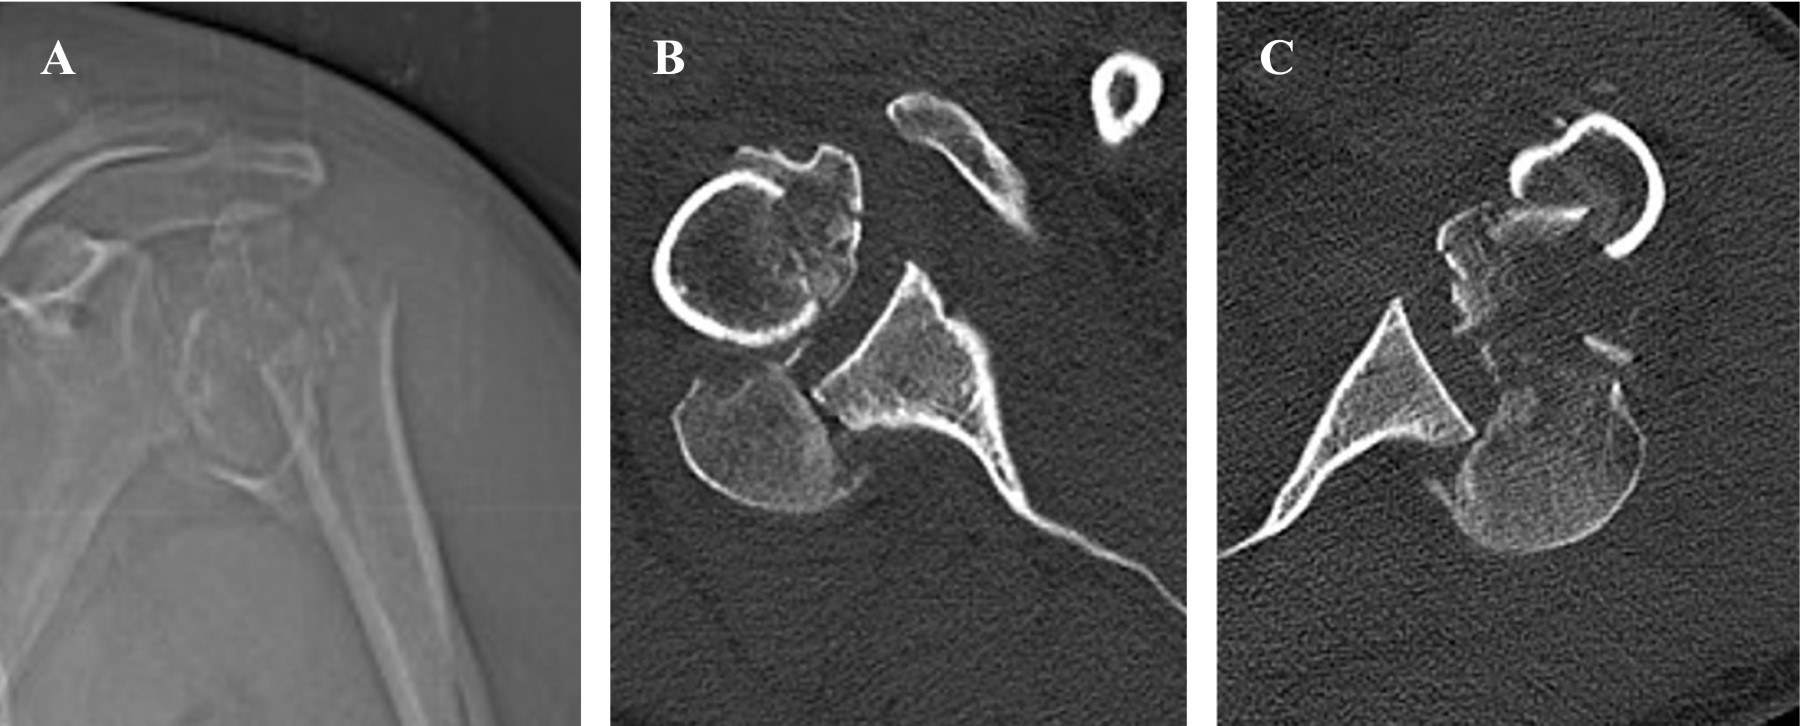

En su evaluación inicial se revisan de detenidamente las radiografías del paciente tomadas al ingreso, que muestran LFGHP derecha (Figura 2A) y luxación simple posterior izquierda (Figura 2B). Esta segunda lesión (luxación posterior simple de hombro izquierdo) no fue diagnosticada en el centro, que derivó inicialmente al paciente y tomó alrededor de 48 horas para ser diagnosticada en nuestro centro.

Se solicitó tomografía computarizada (TC) de ambos hombros para caracterizar mejor las lesiones (Figura 3). Se puede observar en estas imágenes franco agravamiento de la lesión del hombro izquierdo desde el momento del primer estudio radiográfico, posiblemente secundario a la contención física del paciente. Se evidencia por lo tanto, progresión desde una luxación posterior glenohumeral simple izquierda en las radiografías de ingreso (Figura 2B) a una LFGHP en la TC tomada 48 horas después (Figura 3A-C).

En el caso presentado se puede apreciar claramente que en el estudio inicial del paciente no hay fracturas en la zona proximal del húmero izquierdo, observándose 48 horas después una extensa conminución metafisaria en el estudio por TC.